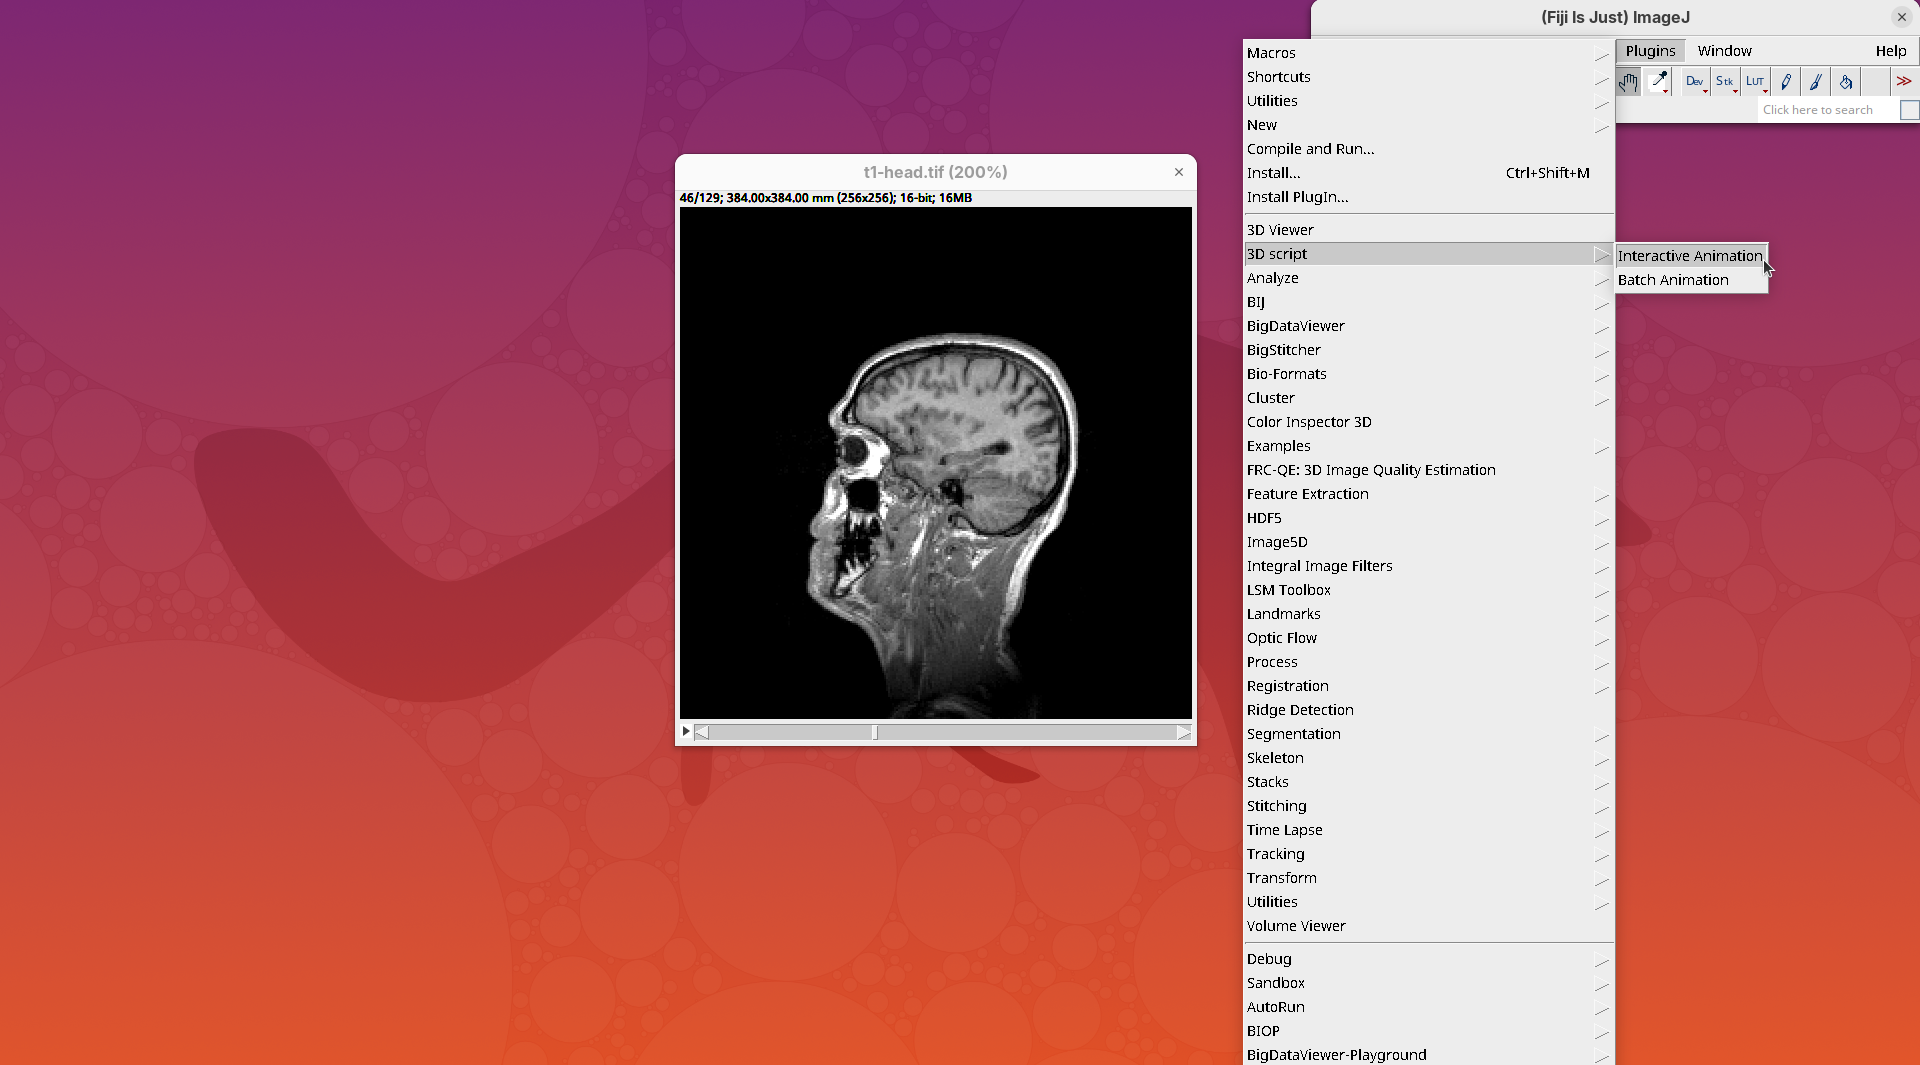

- Go to

Plugins>3Dscript>Interactive Animation.

Two new windows will open: 3D Animation with the initial rendering of the data and Interactive Raycaster with all the fields to control the rendering parameters.